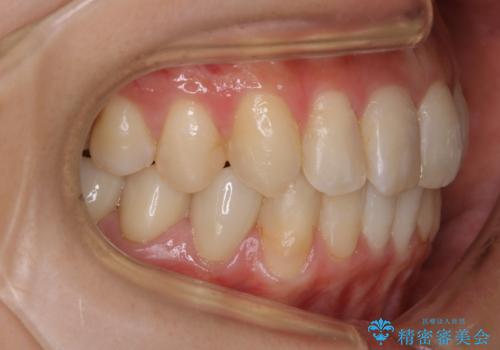

- 前歯のガタつきと噛み合わせの改善を希望してご来院されました。

目立たない装置での矯正治療をとのことでインビザラインを用いた非抜歯矯正を行うこととなりました。